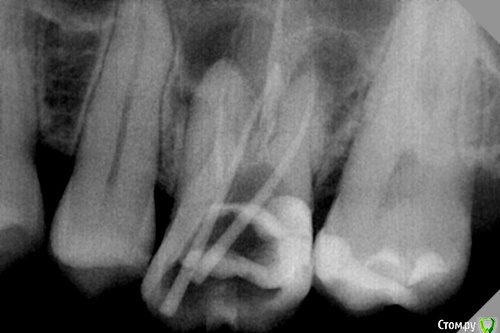

dr.Dre Опубликовано 5 сентября, 2016 Поделиться Опубликовано 5 сентября, 2016 Добрый день коллеги,26 зуб асимптоматический апикальный периодонтит,перелечивание.Мезиальный канал перфорнул,все время попадаю в перфорацию никак не могу зацепить корневой канал.Есть ли смыл в лечение такого зуба? Ссылка на комментарий

Ker Опубликовано 6 сентября, 2016 Поделиться Опубликовано 6 сентября, 2016 Чем перфо сделали? Чем запломбирован канал? Ссылка на комментарий

dr.Dre Опубликовано 6 сентября, 2016 Автор Поделиться Опубликовано 6 сентября, 2016 Чем перфо сделали? Чем запломбирован канал?с -pilot,каналы ещё не пломбировал Ссылка на комментарий

Паращук Роман Опубликовано 6 сентября, 2016 Поделиться Опубликовано 6 сентября, 2016 Я вот никак не пойму как ручным файлом,тем более с-пилотом сделать перфо?! Думаю вы изначально сильно бором поработали. 2 Ссылка на комментарий

vse32 Опубликовано 6 сентября, 2016 Поделиться Опубликовано 6 сентября, 2016 Думаю вы изначально сильно бором поработали. Или УЗ. Тоже при определенном упорстве делает перфо на ура. Ну и, черт возьми - угол то совсем другой. Измените направление и ковыряйте. Ссылка на комментарий

dr.Dre Опубликовано 6 сентября, 2016 Автор Поделиться Опубликовано 6 сентября, 2016 чем были запломбированы.p.s. точно не бором?резорцином,я думаю ультразвуком Ссылка на комментарий